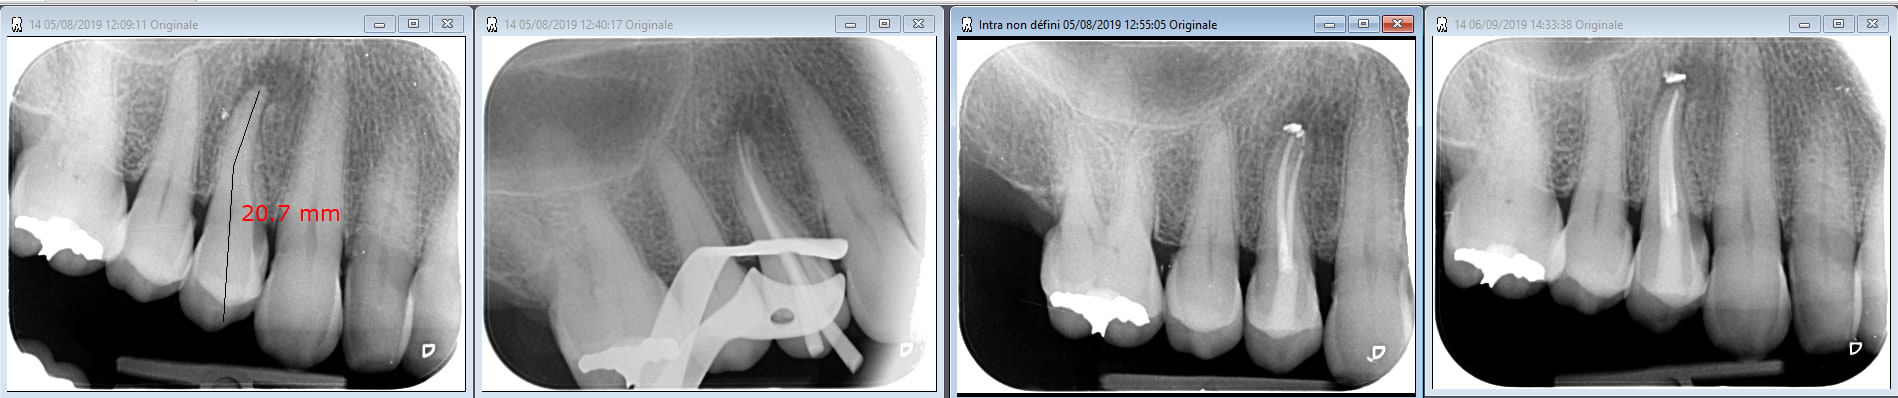

Patiente 69 ans fumeuse +++ bruxisme ++

necrose de 14 consécutive a une fissure objectivée visuellement lors de la préparation de la cavité d'accès réalisée sans anesthésie...

Douleur (moindre mais toujours présente) aujourd'hui a un mois du traitement… image radio identique a la per-op...

Nous avons une 14 nécrosée, objectivable radiologiquement, pas de doute là dessus.

Le traitement est radiologiquement parfait, donc à moins d'un improbable canal accessoire, on ne fera pas mieux de ce côté là.

Quand il y a une felure, je fais soit un cerclage soit une reconstitution au compo pour essayer de coller les morceaux, et en sous occ. Si il y a encore une douleur apres ca, elle a plus de chance de provenir de la belle peche qu'elle se traine. Tu as un depassement de CaOH, je vois mal ta LIPOE guerir spontanement.